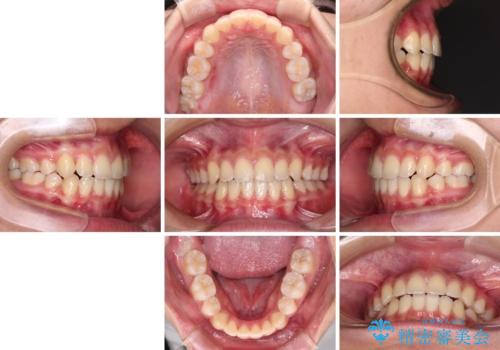

気がつくと口が開いてしまう 閉じにくい口元改善の抜歯矯正

- 前歯のデコボコと八重歯を気にして来院された患者様です。

本人はあまり実感はありませんでしたが、同席されたご家族より口がすぐに開いてしまうことを指摘されていました。

口元に力の入る歯列であったため、上顎左右第一小臼歯4本を抜歯するワイヤー矯正を行うこととしました。

当初は八重歯やデコボコが一番気になっていましたが、抜歯矯正により口元の突出感が改善されるにつれ、口の閉じやすさを実感するようになってきました。

部活動で調整来院に来られないことがしばしばあり、期間は予定よりもかかりましたが、きれいに仕上げることができました。